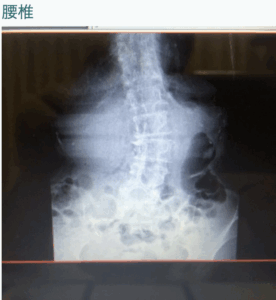

自分の施術を見直して何度も施術しましたが、一向に改善しないでいると、いつもその方が行く内科の病院で検査を促されX線を撮影。

すると、関節ネズミが複数出来ているとのことでした。整形で検査済みといっても、4年も経てばこういったこともあると勉強になりました。

そのことがあってから、同じくメンテナンス段階だった【変形性膝関節症】の70代女性が、ご主人が入院・介護・死去とバタバタ続きで調子を崩し、膝の痛みがきつくなってなかなか手こずっている方がおられたので、今回の反省を踏まえ検査してもらいました。

結果は、変形の進行度は末期であるが、ネズミはない。

その病院は以前私が勤めていた所なので、写真を貰えるのですが、その写真を見ていると画像の矢印部分に隙間を作ればいいのではないかと気付き、膝関節中央よりやや外側にスペースをあける施術をしたところ

劇的に改善!!! 施術後2回目来院時も効果継続。

末期の変形性膝関節症の方でも解剖学的に正しい位置に行けば改善する! 画像診断とパーフェクト整体。新たな発見があるかも?